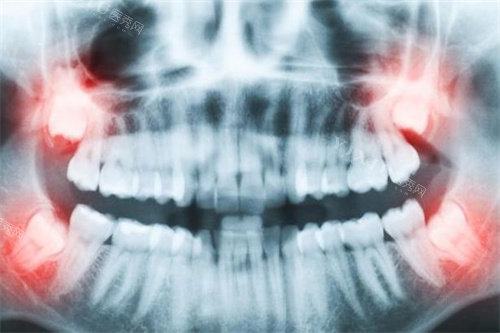

看设备:正规机构应配备CBCT、智能化口扫仪、种植机等基础设备,警惕仅用普通X光片的机构。

查病例:要求查看医生同类病例术前术后CT对比,重点观察骨结合情况及牙龈形态。